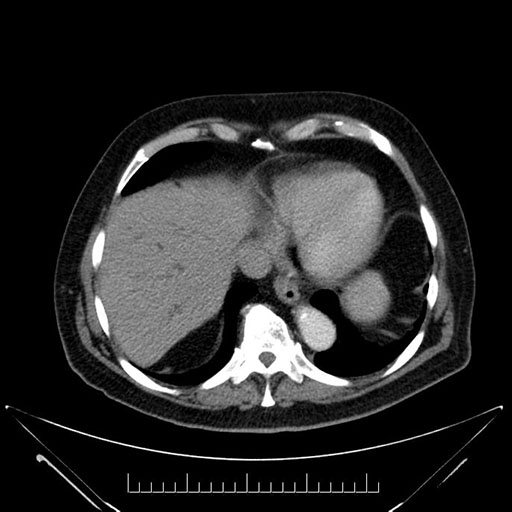

Axial - 3 months prior